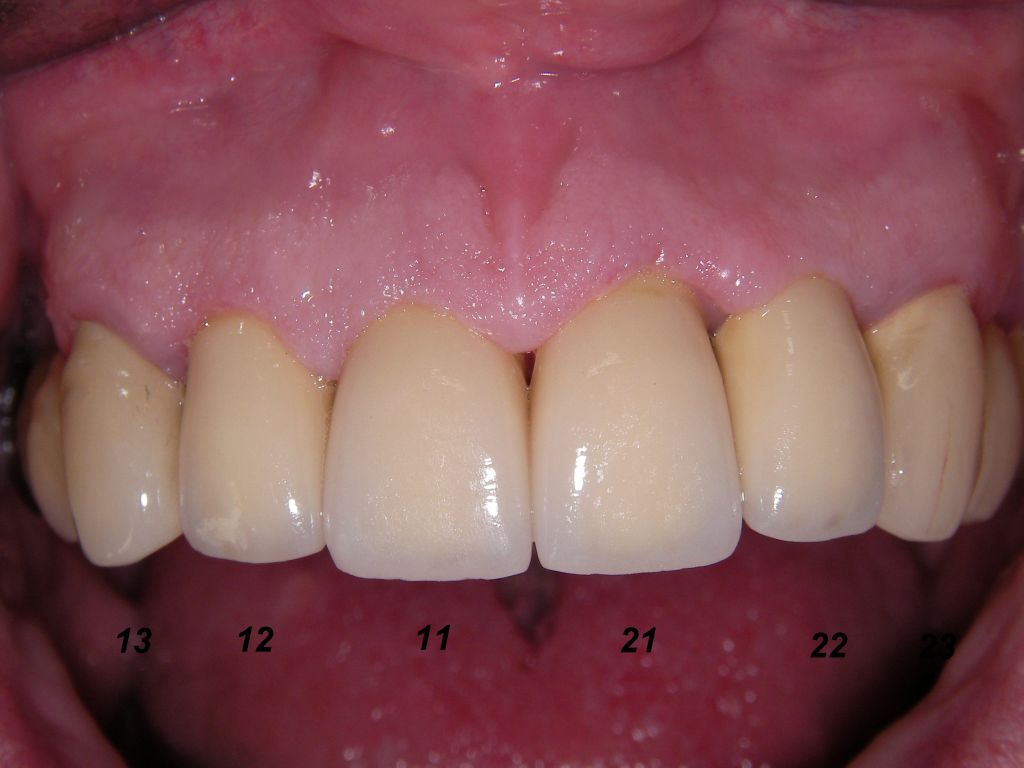

Eine Vollkeramikkrone (Keramik ohne Metallunterbau) ist demgegenüber bruchanfälliger. Der Vorteil der Vollkeramikkrone ist allerdings, daß bei Rückgang des Zahnfleisches auch nach vielen Jahren kein dunkler Metallrand sichtbar werden kann. Allerdings kann man diesen Metallrand auch sehr schmal gestalten, wie das folgende Beispiel zeigt. Wegen der starken Zerstörungen mußte der Kronenrand tief unter das Zahnfleisch gelegt werden. Das ist einerseits ungünstig, weil es Zahnfleischentzündungen fördern kann (die hier aber nicht zu sehen sind), andererseits günstig, weil nicht zu befürchten ist, daß das Zahnfleisch so weit zurückgehen wird, daß man den Kronenrand sehen wird. Wenn man nicht so weit unter das Zahnfleisch mit dem Kronenrand gehen muß und mehr Platz hat, kann man auch einen keramischen Rand (eine "keramische Stufe") wählen. Das erhöht die Laborkosten, aber man hat die Sicherheit, daß es langfristig keinen sichtbaren Metallrand geben kann. Auch eine Vollkeramikkrone ist natürlich möglich. Oft ist nach vielen Jahren aber gar nicht die Krone das Problem, sondern die dunkle Zahnwurzel, die vom Zahnfleisch entblößt wird. Wie man unten sieht, sind insbesondere wurzelbehandelte Zähne sehr dunkel. Hier hilft dann doch nur wieder, mit dem Kronenrand tief unter das Zahnfleisch zu gehen, um die dunkle Wurzel abzudecken. Patient, 67 Jahre. Die Bilder sind alle zur Vergrößerung anklickbar! |

Links die Kronen aus dem Dentallabor "Heitmeyer Zahntechnik", Osnabrück. Man sieht praktisch keinen Metallrand. Der Patient war zur Farbbestimmung im Dentallabor - so halten wir es praktisch immer. Rechts das Ergebnis bei der 1. Nachkontrolle am 27.3.05. Das Zahnfleisch muß sich noch etwas erholen. |